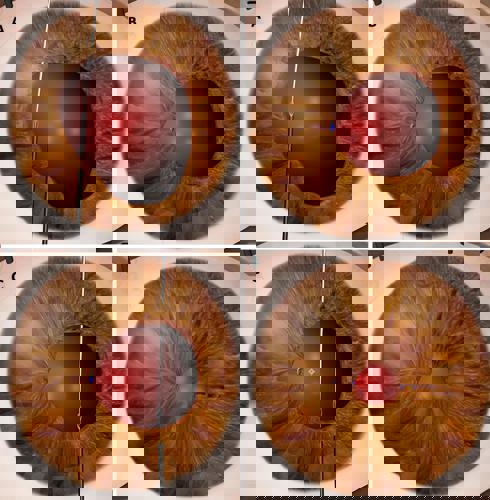

FIGURE: A) Single-pass, four-throw pupilloplasty bite is taken on one side of the pupil using 10-0 prolene suture on a long, thin needle. A 30-gauge needle is passed through a paracentesis and taken through the pupil on the other side. The first needle is railroaded into the 30-gauge needle to bring it out of the paracentesis; B) A loop is brought out and the leading end of the suture is cut and passed four times through the loop followed by pulling both ends apart to close the knot; C) A similar knot is taken on the other side; D) Multiple knots are taken until the pupil is small and centred on the patient-fixated, coaxially sighted corneal light reflex. A vitrector is used on a low cut rate and low vacuum to cut the pupil to adjust final size, shape, and centration.